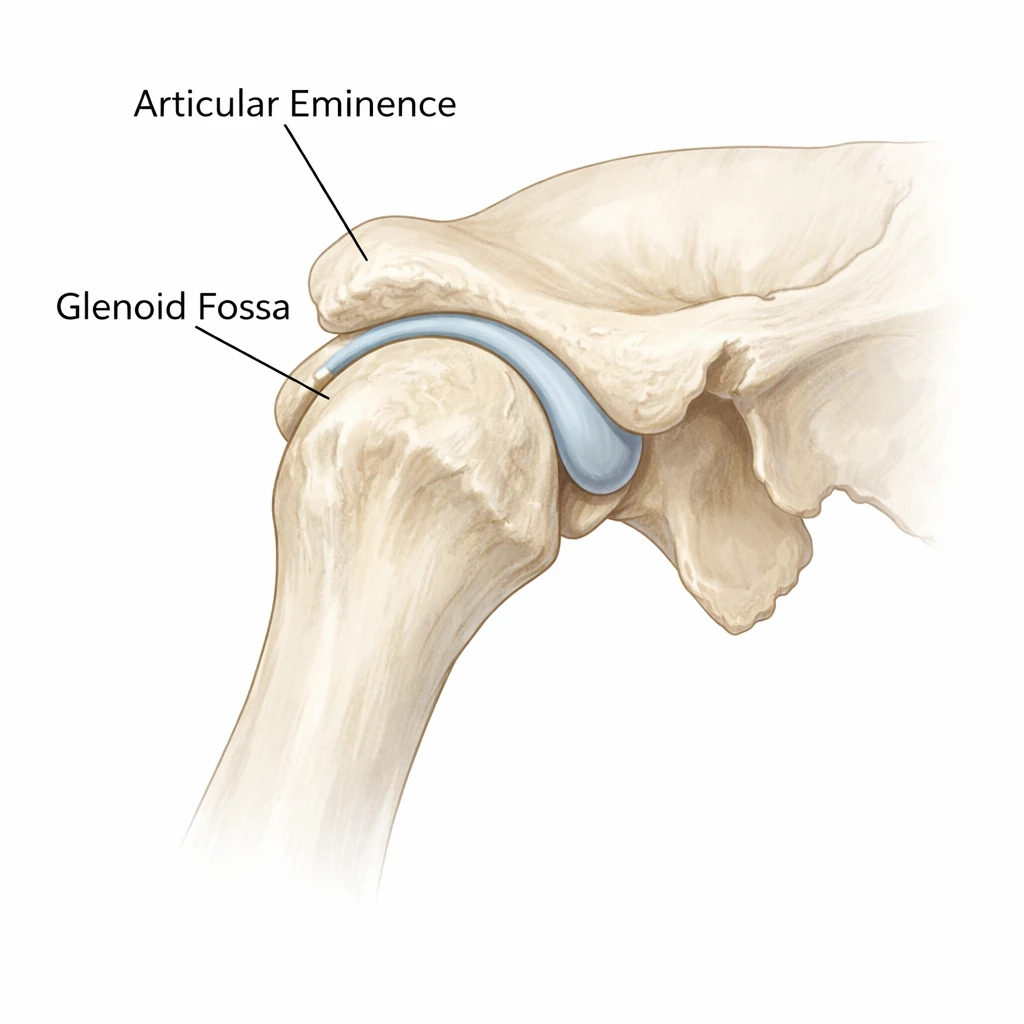

حفره گلنوئید (Glenoid Fossa)

Glenoid Fossa فرورفتگی‌ای در استخوان گیجگاهی است که کندیل فک پایین در آن قرار می‌گیرد.

دیواره خلفی این حفره نازک‌تر و حساس‌تر است و سقف آن نیز ضخامت کمی دارد. در حالت دهان بسته، کندیل درون این حفره قرار می‌گیرد.

به دلیل نازکی استخوان، این ناحیه در برابر تروما و فشارهای غیرطبیعی آسیب‌پذیر است.

glenoid fossa and articular eminence TMJ

برجستگی مفصلی (Articular Eminence)

Articular Eminence برجستگی استخوانی در جلوی Glenoid Fossa است که نقش مهمی در حرکت لغزشی کندیل ایفا می‌کند.

در هنگام باز شدن دهان، کندیل از حفره گلنوئید خارج شده و روی این برجستگی می‌لغزد. شیب Articular Eminence مستقیماً بر دامنه و الگوی حرکت فک تأثیر می‌گذارد.